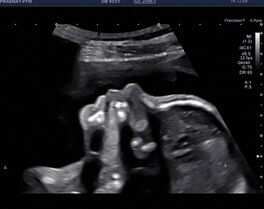

Organscreening (Fehlbildungsausschluss)

Diese „zweite“ große Ultraschalluntersuchung wird am besten in der 20+0 SSW bis 23+0 SSW durchgeführt.

Beim Organscreening oder Fehlbildungsausschluss wird die Entwicklung Ihres Kindes genau beurteilt. Nach den Richtlinien der DEGUM zeigen und erklären wir Ihnen umfassend alle bedeuteten sonografischen Merkmale Ihres Kindes. So können wir Ihn in der Regel zeigen, dass sich Ihr Kind ganz normal entwickelt.